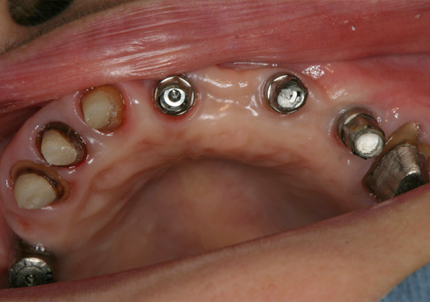

患 者 : E.Y様 女性

主 訴 : 脊髄カリエスの既往により右側上顎欠損、インプラント再治療を含む全顎的な治療希望する

初診日 : 2006年4月24日

既往歴 : 20年前、他院にてバイオセラムインプラント埋入、不良補綴となる

1.初診時(2006年5月)

2.上顎補綴物除去

3.上顎補綴物除去、旧インプラント除去手術後(骨吸収後)